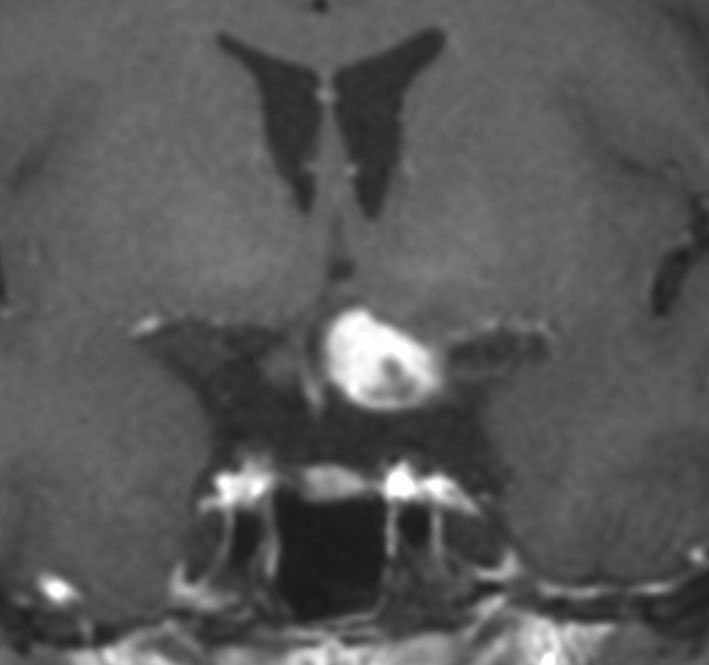

幼児の視路の毛様粘液性星細胞腫です。T2強調画像(左側)で白く高信号に写るのが特徴です。ガドリニウム増強ではまだらになっていますが,均一に真っ白に高信号になることも多いです。乳幼児のものは,ドロドロに柔らかい腫瘍です。

生後7カ月の幼児です。目が揺れるようになり(振り子様眼振)眼科を受診して腫瘍が発見されました。小児脳腫瘍の治療ができる病院へと紹介されました。

1ヶ月後にまたMRI検査がされました。乳児ですから検査にも麻酔が必要です。腫瘍は明らかに大きくなっています。左視神経から視索の腫瘍化が著しいので右側だけかすかに視力が残っているかもしれません。視力は明かりがわかる程度(明暗弁)と評価されました。